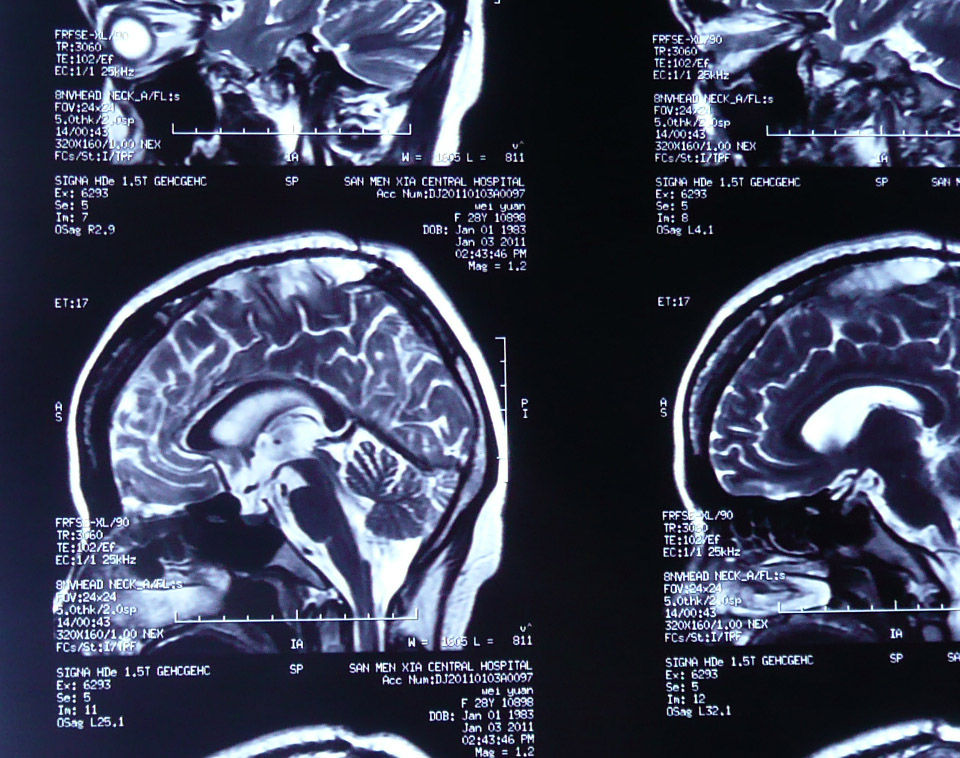

ommaya囊植入术图谱

科普幻灯片——ommaya储液囊在神经系统疾病中的应用 - 好大夫在线